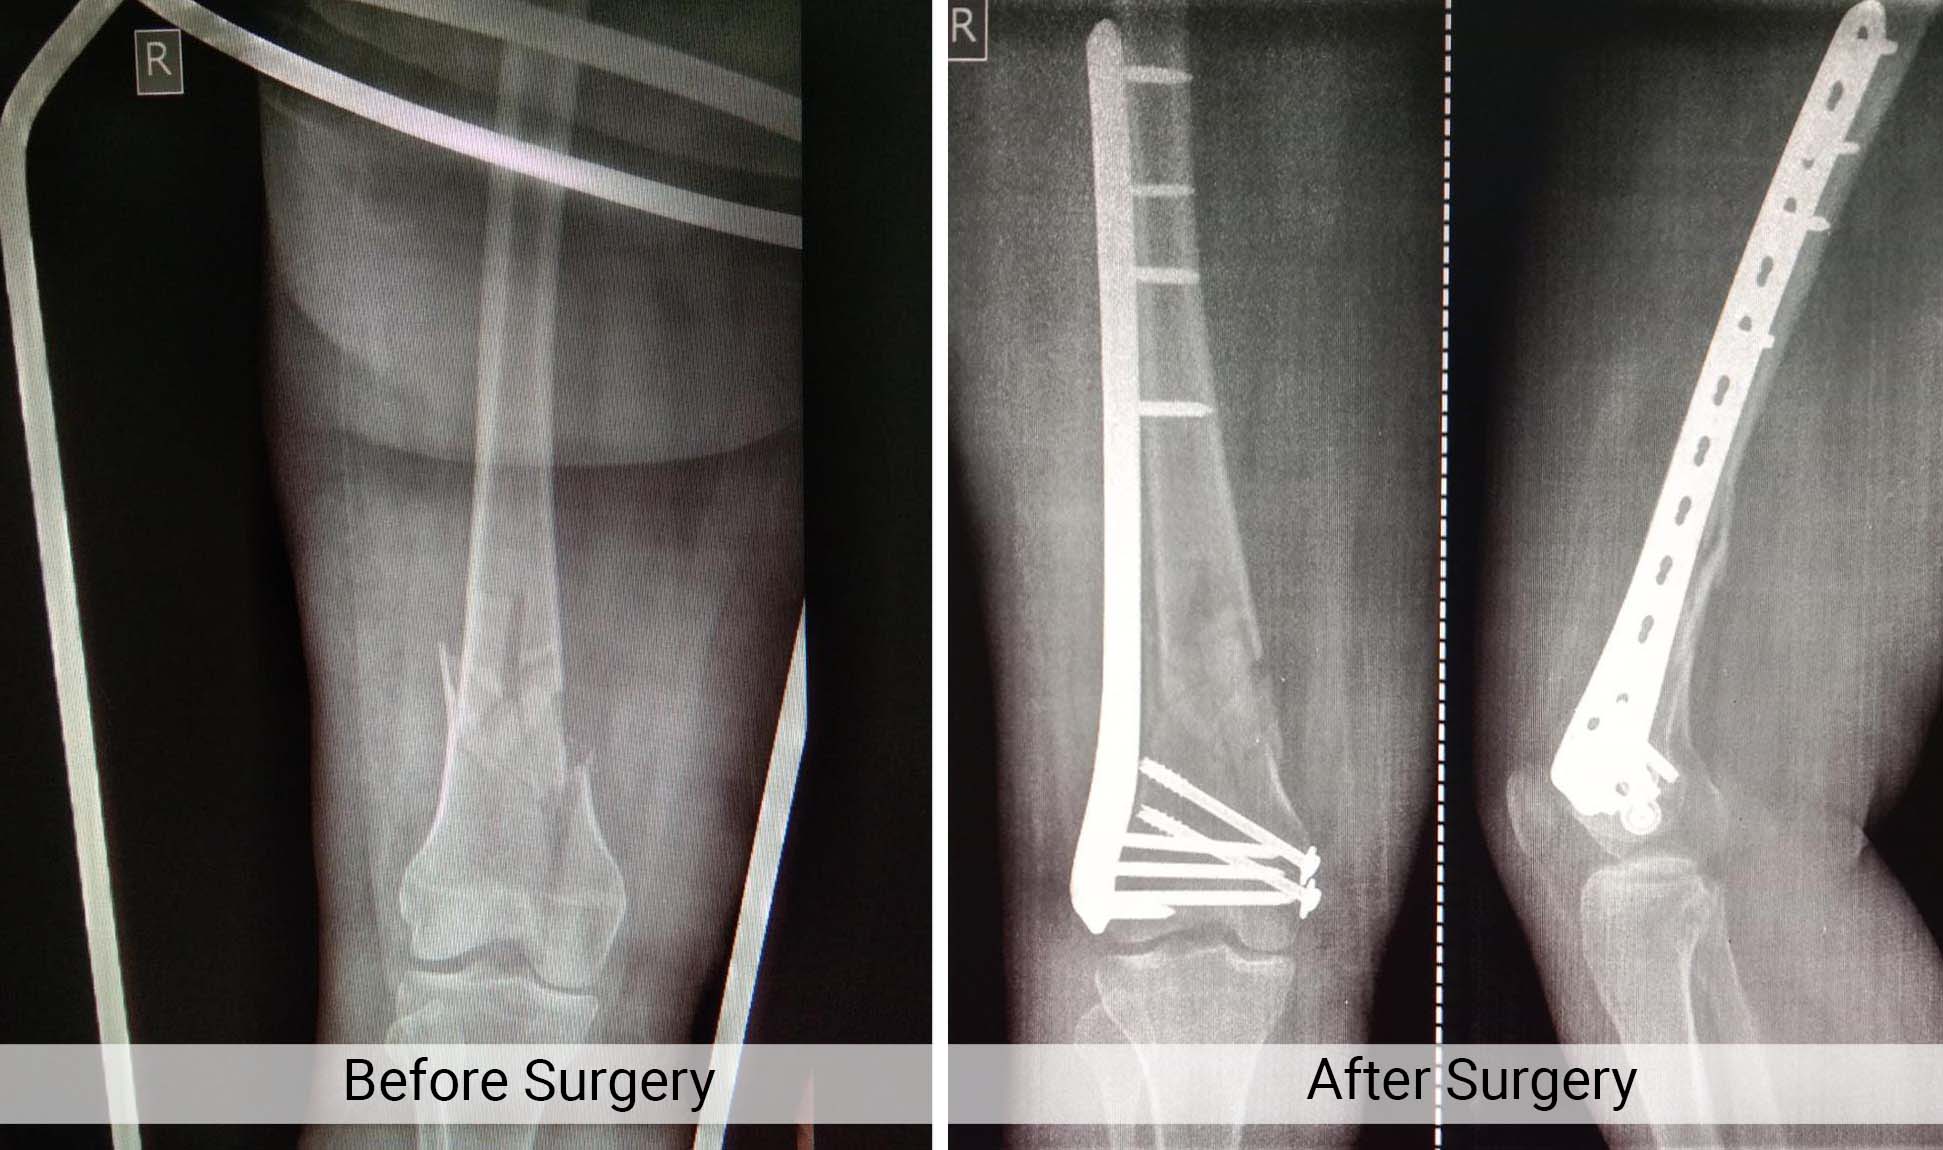

Trauma Fracture